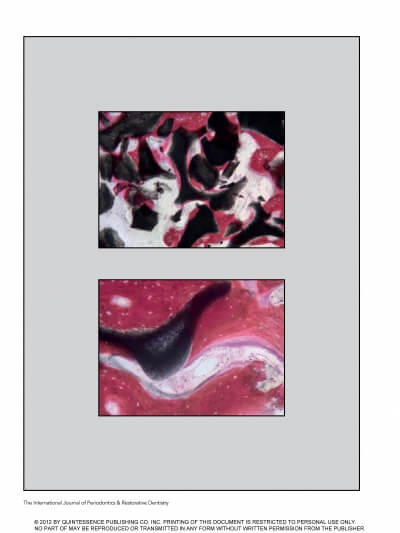

Оба установленных имплантата были плотно защищены «сыпучей мембраной», эта манипуляция предотвращает краевую резорбцию кости, тем самым сводит на нет возможность проявления периимплантита как такового.